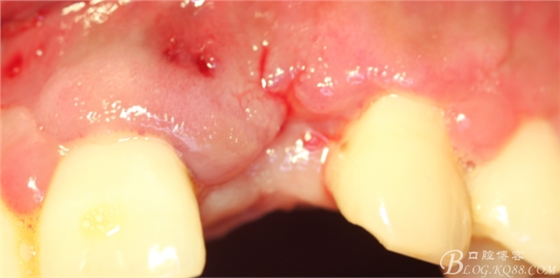

事實(shí)證明,我的做法沒有錯(cuò)誤,一個(gè)月后,軟組織健康愈合。鄰牙軟組織沒有退縮。

再次翻瓣。